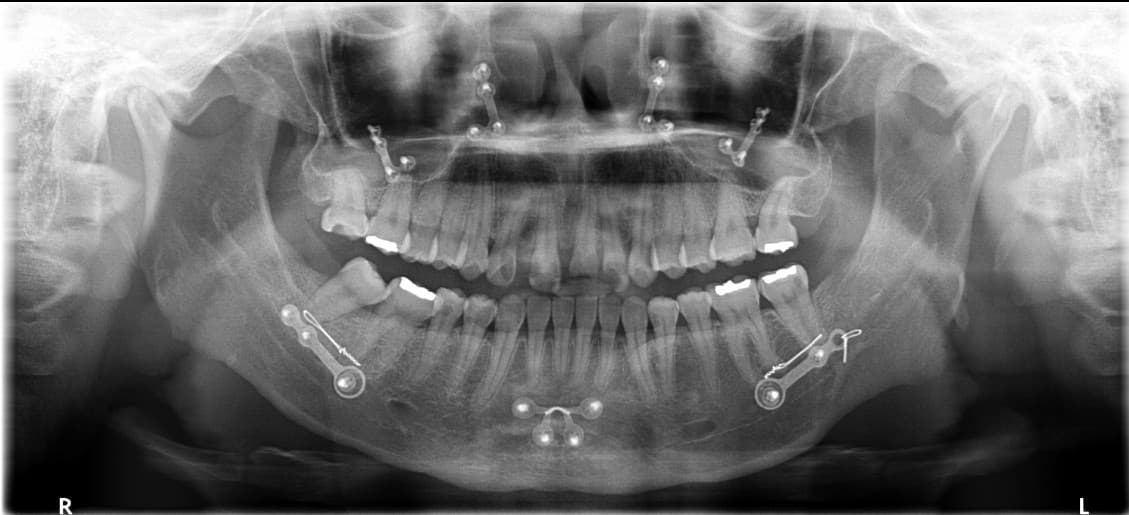

Implant hướng dẫn kỹ thuật số

Implant răng cửa · Bà K●● · Nữ, 50 tuổi

Sau

Implant răng cửa · Ông L●● · Nam, 60 tuổi

Implant răng hàm · Ông P●● · Nam, 50 tuổi